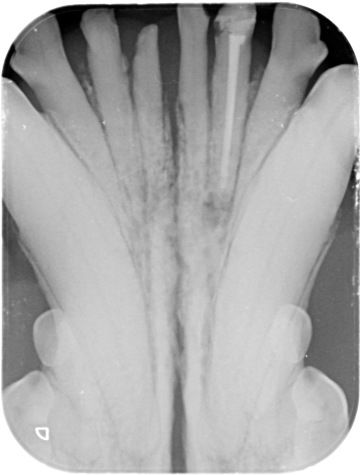

Endodontické ošetření znamená ošetření vnitřního prostoru zubu, laicky řečeno ošetření kořenových kanálků zubu. Je nutné ho provést vždy, když dojde v zubní dřeni k patologickému procesu, tedy zánětu nebo odumření, ať už následkem příliš velkého zubního kazu, nebo úrazu.

Léčba kořenových kanálků (endodoncie) je léčba, která zahrnuje odstranění infikované dřeně z kořenového kanálku zubu, sterilizaci (dezinfekci) kanálku a nahrazení odstraněné tkáně zubním materiálem. Kořenový kanálek je přístupný přes korunku zubu. Jakmile je kořenový kanálek naplněn zubním materiálem, přístup přes korunku je vyplněn (obnoven), aby se zabránilo dalšímu přístupu bakterií do kořenového kanálku. Konečným cílem je zabránit bakteriím v pronikání do zubu. Standardní terapie kořenových kanálků umožňuje domácímu mazlíčkovi zachovat si zub (ačkoli již nežije) a zachovat jeho funkci, protože strukturální integrita zubu byla zachována.

Když si pes zlomí zub a obnaží dřeň, bakterie a zbytky z úst proniknou do středu zubu. V důsledku toho se rozvine bolestivý zánět dřeně (pulpitida), který nakonec způsobí odumírání nervů a krevních cév (nekróza dřeně). Bakterie pronikají ven z kořenového hrotu (špička kořene obklopená kostí) a infikují kost kolem kořene (apikální parodontitida). Pulpitida i apikální parodontitida jsou velmi bolestivé. Vzhledem k tomu, že infekce zubu a následně také infekce kosti kolem kořene je vysoce pravděpodobná, zlomené zuby s obnažením dřeně by měly být co nejdříve ošetřeny buď standardní terapií kořenových kanálků tj. endodonticky, nebo extrakcí.